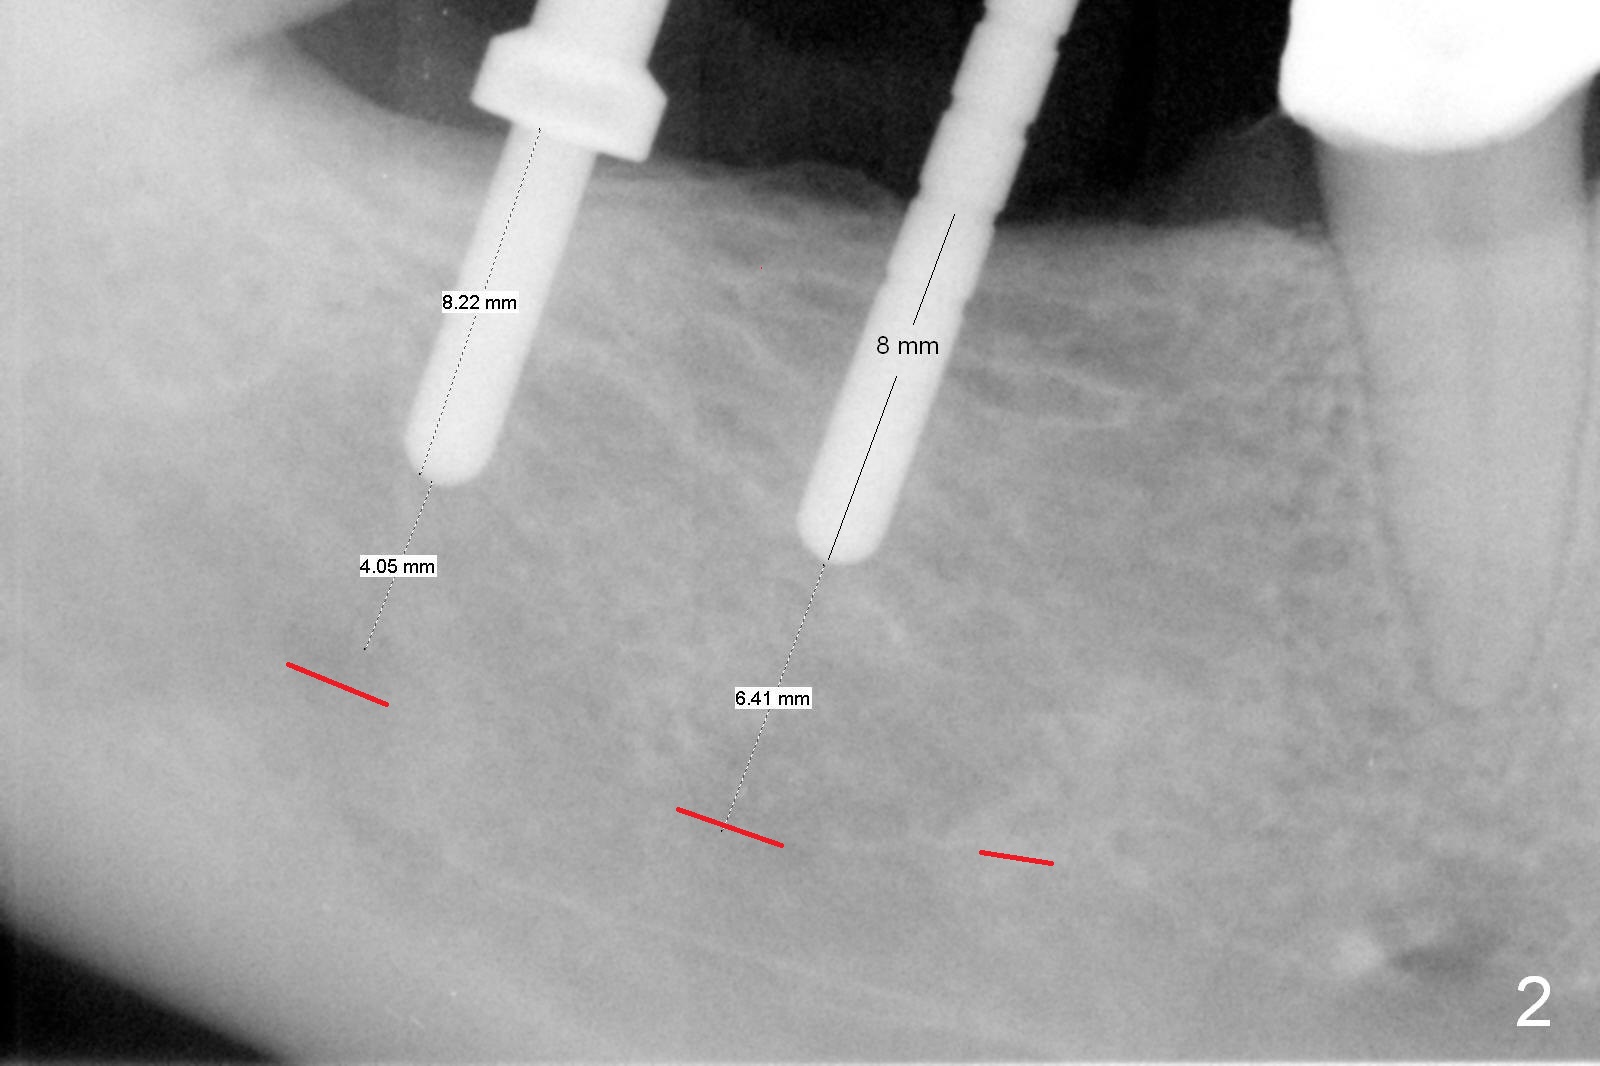

A preop photo shows different shape of pontics at #30 and 31 (Fig.1 <), suggesting different width of the edentulous ridge.  Two of 8 mm parallel pins are inserted for position and trajectory (Fig.2 (red dashed line: the superior border of the Inferior Alveolar Canal).  When they are removed from the osteotomy sites, the narrow ridge at #30 is shown (Fig.3).  A 3x12 mm 1-piece implant is placed at #30, while a 4.5x10 mm 2-piece one at #31 (Fig.4,5).  It appears that it is necessary to place an implant at #32, since the tooth #1 is present (Fig.5).  The suggestion is rejected by the patient due to finance.  After extraction of the tooth #32 and insertion of collagen plug, an immediate splinted provisional is fabricated to cover the #32 socket as well (Fig.6).  The provisional is modified (to remove the portion that covers #32 socket) 3-4 weeks postop.